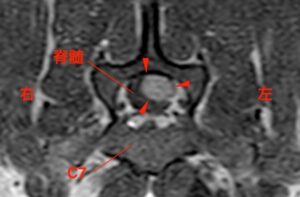

![[MRI、横断像(T7)、造影T1強調画像]](https://saitovet.com/wp-content/uploads/2025/09/2-2-300x197.jpg)

その後、病理検査の結果

→「悪性末梢神経鞘腫瘍(MPNST)」と診断

通常は神経の通り道をたどって、脊柱管に入り込むように見えるのが特徴。